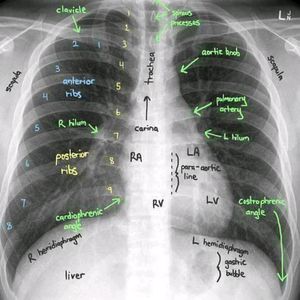

Radiology

Pulmonology